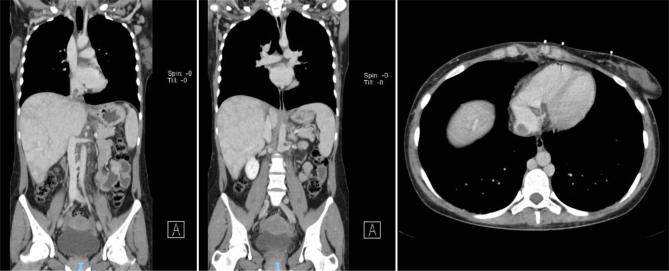

This article describes a case of a 26-year-old female with a history of Evan's syndrome who presented with severe exertional dyspnoea and abdominal discomfort. The patient was diagnosed with chronic Budd-Chiari syndrome, a rare vascular disorder characterized by obstruction of the hepatic vein. We discuss the risk factors, the clinical manifestations, and diagnostic methods for Budd-Chiari syndrome, as well as the possible association with an underlying incomplete systemic lupus erythematosus. The importance of close follow-up and timely diagnosis for preventing disease progression and reducing mortality is emphasized. The article concludes by highlighting the need for further monitoring to identify any symptoms or signs suggesting a progression to complete lupus erythematosus.

本文描述了一例26岁患有伊文氏综合征的女性病例,该患者出现严重劳力性呼吸困难和腹部不适。患者被诊断为慢性布加综合征,这是一种罕见的血管疾病,其特征为肝静脉阻塞。我们讨论了布加综合征的危险因素、临床表现、诊断方法,以及与潜在的不完全系统性红斑狼疮的可能关联。强调了密切随访和及时诊断对于预防疾病进展和降低死亡率的重要性。文章最后强调需要进一步监测,以识别任何提示进展为完全性红斑狼疮的症状或体征。